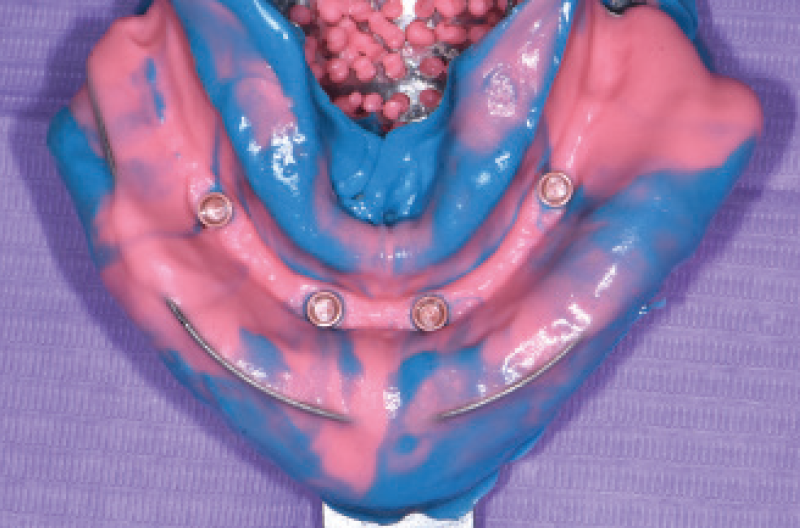

Siamo cos├¼ giunti al mese di gennaio 2020 per la presa delle impronte definitive. Ho rimosso con grande facilit├Ā e velocit├Ā le due Toronto conometriche provvisorie con lŌĆÖaiuto di un comune martelletto levacorone. Ho posizionato delle cappette Mobile sui monconi conometrici, utilizzandole come transfer, e preso unŌĆÖimpronta con un cucchiaio chiuso. Infine ho riposizionato e riattivato in pochi secondi le due Toronto conometriche (Figg. 39-43).

Fig. 39 – Vista occlusale dei monconi MUA-Conic a guarigione avvenuta

Fig. 40 – Situazione clinica al momento della presa dellŌĆÖimpronta

Fig. 41 – Cappette Mobile usate come transfer per la presa dellŌĆÖimpronta

Fig. 42 – Impronta inferiore

Fig. 43 – Impronta superiore